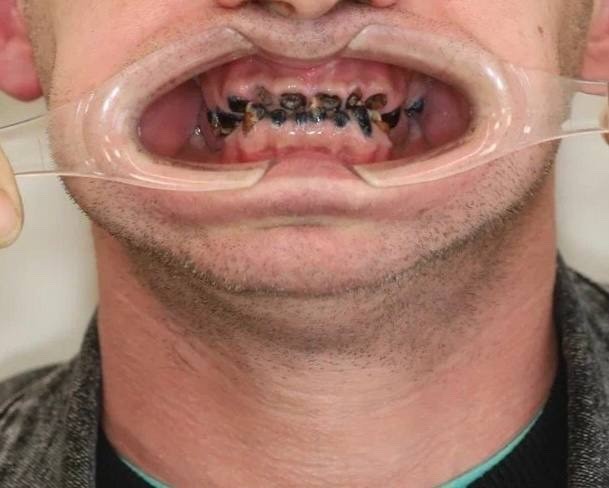

Фотографии до и после: Имплантация

На странице представлено портфолио стоматологий Самары с фото работ до и после имплантации зубов. Мы собрали разные клинические случаи: одиночные импланты, восстановление нескольких зубов и полная реконструкция зубного ряда. Здесь вы можете видеть, как выглядят восстановленные зубы, меняется форма улыбки после процедуры. Изучите результаты до и после имплантации зубов, чтобы оценить качество работы врачей и выбрать стоматологию в Самаре, которая поможет вернуть функциональность и эстетику вашей улыбке.

Имплантация All-on-4

Имплантация All-on-4

Имплантация All-on-4

Имплантация All-on-4

Имплантация All-on-4

Имплантация All-on-4

Имплантация All-on-4

Имплантация All-on-4

тотальная реабилитация пациента по методике All-on-4

Имплантация All-on-4

тотальная реабилитация пациента по методике All-on-4

Имплантация All-on-4

тотальная реабилитация пациента по методике All-on-4

Имплантация All-on-4

тотальная реабилитация пациента по методике All-on-4